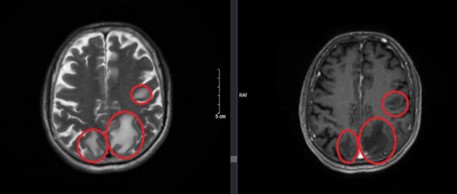

Chụp cộng hưởng từ sọ não: Nhu mô não vùng trên lều tiểu não có các nốt tổn thương nhu mô não dưới vỏ thuỳ trán trái, thùy đỉnh hai bên và thùy chẩm phải, đường kính ổ tổn thương lớn nhất 12mm, ngấm thuốc mạnh sau tiêm, có phù não rộng xung quanh.

Hình 2: Hình ảnh cộng hưởng từ sọ não: Các nốt tổn thương nhu mô não ngấm thuốc mạnh sau tiêm, có phù não rộng xung quanh (vòng tròn màu đỏ)(B: Thùy chẩm, A,C: Thùy đỉnh)

Hình ảnh chụp cộng hưởng từ sọ não sau 3 chu kỳ điều trị hóa chất:

Trước điều trị

Sau điều trị

Hình 4: Hình ảnh chụp cộng hưởng từ sọ não trước và sau điều trị

Nhận xét: Trước điều trị hóa chất xuất hiện hình ảnh nhu mô não có các nốt tổn thương nhu mô não hai bên ngấm thuốc mạnh sau tiêm, có phù não rộng xung quanh, tuy nhiên sau điều trị hóa chất 3 chu kỳ, không còn thấy hình ảnh tổn thương thứ phát tại não.